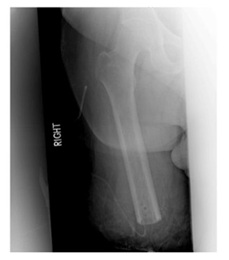

Transfemoral amputations have seen an improvement in surgical ideology over time. Traditionally, according to the general and vascular surgery literature, muscle transection when performing this procedure can be done without any stabilization. Contrary to that, orthopedic principles indicate that when performing a transfemoral amputation a myodesis is to be performed to limit the likelihood of developing a flexion or abduction contracture (Figure 1). With either contracture the amputee would be unable to generate sufficient power to manipulate prosthesis [9]. When performing the adductor myodesis, the hip must not be flexed as this would create an iatrogenic flexion contracture that would only complicate post-operative rehabilitation. Maximizing length in the extremity assists patients with transfers and sitting. A long posterior skin flap with adequate muscle coverage over the beveled femoral diaphysis and adductor myodesis allows for a cosmetic residual limb that is amenable to prosthesis fitting and eventual ambulation.

Figure 1: AP radiograph of the right femur following transfemoral amputation with drill holes in the distal femoral diaphysis for the adductor myodesis.